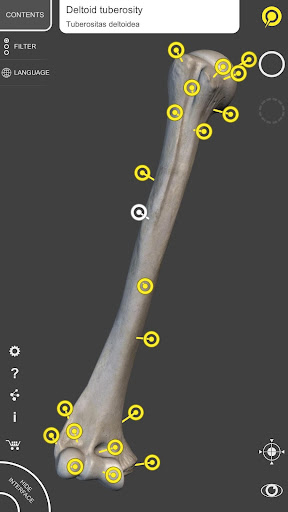

Mỗi xương của bộ xương người đã được tái tạo ở dạng 3D, bạn có thể xoay và phóng to từng mô hình và quan sát chi tiết từ mọi góc độ.

Bằng cách chọn mô hình hoặc ghim, bạn sẽ được hiển thị các thuật ngữ liên quan đến bất kỳ bộ phận giải phẫu cụ thể nào, bạn có thể chọn từ 12 ngôn ngữ và hiển thị các thuật ngữ bằng hai ngôn ngữ cùng lúc.

• Bề mặt của bộ xương có kết cấu độ phân giải cao lên đến 4K

• Xoay và Phóng to mọi mô hình trong không gian 3D

• Phân chia theo vùng để có hình ảnh rõ ràng và trực tiếp về từng cấu trúc

• Ghim tương tác cho phép trực quan hóa thuật ngữ liên quan đến mọi chi tiết giải phẫu